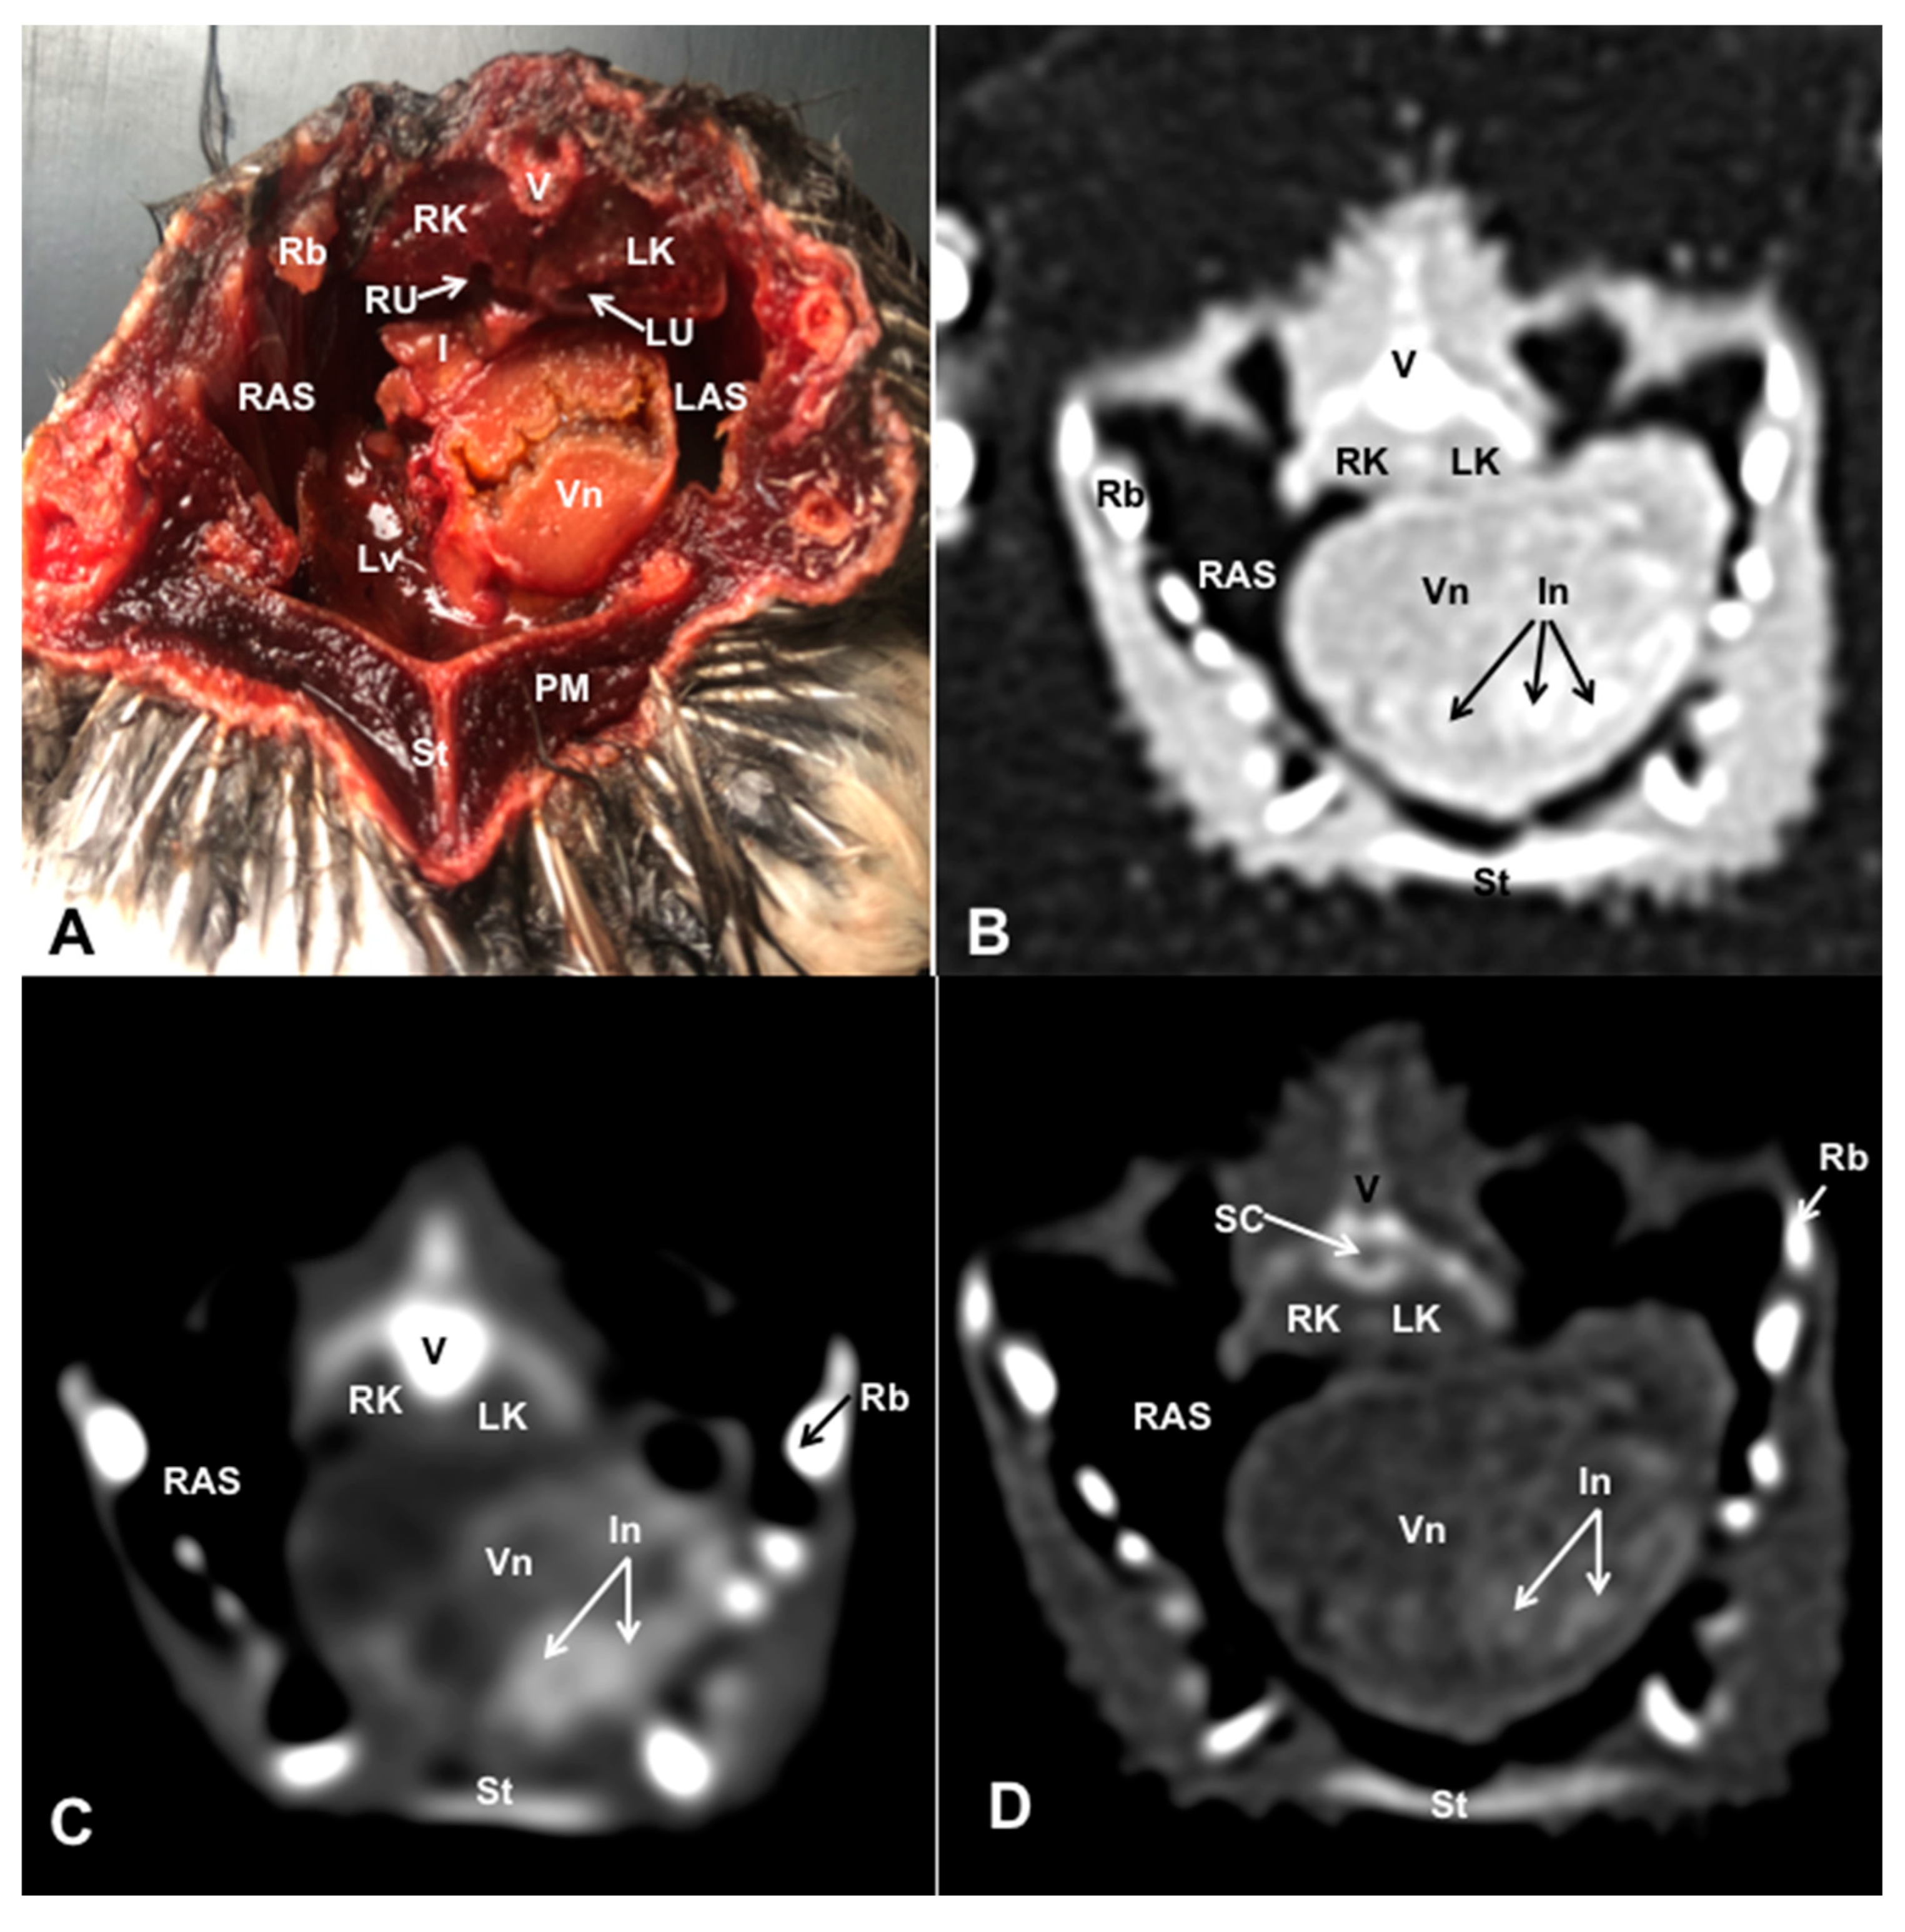

3.1. Anatomical Dissections and Cross-Sections

3.2. Computed Tomography Images